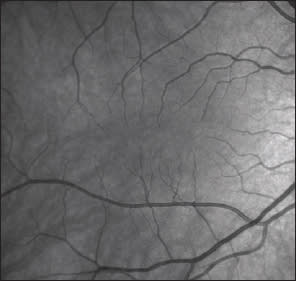

Fundus photography still remains an important imaging tool. There are two methods for capturing fundus photographs: digital fundus photography and confocal scanning laser ophthalmoscopy (cSLO). A digital camera captures a single image of the fundus, whereas cSLO uses laser light projected through a pinhole aperture that isolates a single wavelength to capture an image of the retina point by point. Adjusting the distance of the pinhole aperture captures different depths, and scans are obtained in a raster pattern. cSLO uses lasers of different wavelengths to add false color to the fundus image; however, digital fundus photography captures a truer color image. cSLO can make it more difficult for patients to stay still during image capture due to the laser light intensity, but fast acquisition speeds and after-image processing help correct movement artifacts. cSLOs can use longer wavelengths, which make them ideal to capture images for FAF and indocyanine green (ICG) angiograms.5

The two techniques for imaging vasculature are FA and ICG. A combination of phthalic acid with the plant resin resorcinol is used as the dye for FA, which fluoresces at a peak around 530 nm.6 Fluorescein leaks from damaged retinal vessels and can be used for evaluation of macular edema, venous occlusions and diabetic retinopathy. It delineates areas of choroidal nonperfusion in diabetic retinopathy and vascular leakage in choroidal neovascular membranes. ICG uses a tricarbocyanine dye that has a fluorescence peak around 800 nm. It is highly protein-bound and thus stays within choroidal vasculature better than fluorescein, which permits much-improved evaluation of the choroid. This advantage has made ICG the gold standard for diagnosis of the choroidopathies, including central serous retinopathy. ICG has milder side effects than FA for the most part; however, since it is iodine based, it is contraindicated in patients with iodine allergy or seafood allergy due to cross-reaction.7

2. FA vs. ICG

Advantages: Evaluate proliferative diseases of the retina and choroid.

Limitations: Poor view of choroidal vasculature; invasive—requires injection.

Optimal Uses: Diabetic retinopathy, CNV, vein occlusion.